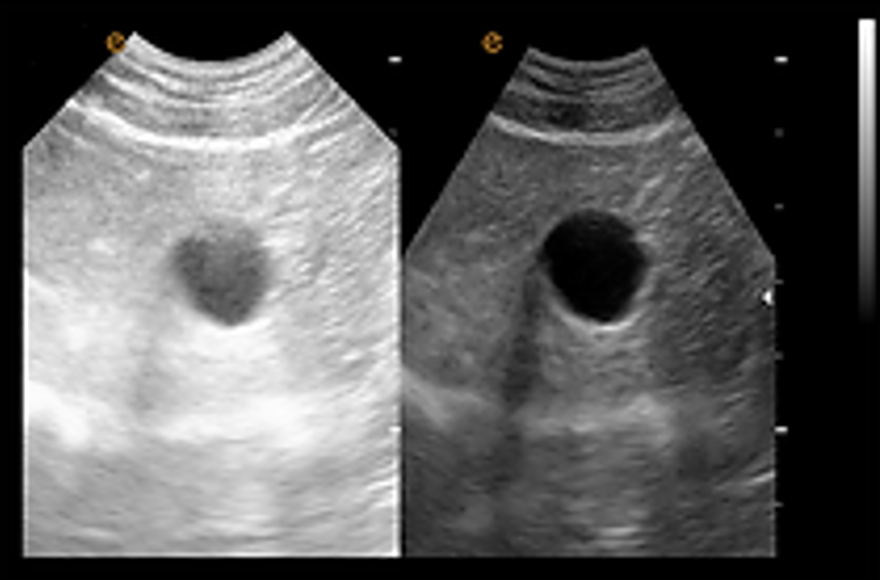

เทคโนโลยีลดจุดรบกวน ePure + เทคโนโลยีลดจุดรบกวน (Speckle Reduction Technology) เป็นเทคโนโลยีที่ช่วยลดสัญญาณรบกวนที่เกิดจากคลื่นสะท้อน (echo) ได้อย่างมีประสิทธิภาพ พร้อมทั้งปรับความสม่ำเสมอของชั้นเนื้อเยื่อต่างๆ ให้เหมาะสม ส่งผลให้ได้ภาพคุณภาพสูงที่มีความคมชัดและขอบภาพที่ชัดเจน |

eSCI การสร้างภาพเชิงพื้นที่แบบผสม การถ่ายภาพอัลตราซาวด์จากหลายมุมมองในระนาบเดียวกันเพื่อสร้างเป็นภาพที่ประกอบขึ้นจากหลายภาพ (tomographic ultrasound images) ผลลัพธ์ที่ได้จะช่วยลดจุดรบกวน (speckle) เสียงรบกวน (clutter) และข้อผิดพลาดทางเสียงสะท้อน (acoustic artifacts) อย่างมีนัยสำคัญ |

eFCI การสร้างภาพเชิงความถี่แบบผสม เทคโนโลยี eFCI ช่วยสร้างภาพที่มีความละเอียดสูงในความลึกที่ต่างกัน โดยการส่งสัญญาณความถี่สูงและต่ำพร้อมกัน เพื่อให้ได้ภาพที่มีความคมชัดและแม่นยำในทุกระดับความลึก |

การระบุตำแหน่งร่างกายสัตว์และบันทึก ระบบระบุตำแหน่งร่างกายสัตว์ที่หลากหลาย ช่วยให้สัตวแพทย์สามารถเลือกและทำเครื่องหมายได้ทันที เพื่อเพิ่มความสะดวกและประสิทธิภาพในการวินิจฉัย ชุดซอฟต์แวร์สัตวแพทย์ระดับมืออาชีพ จากประสบการณ์ความต้องการของสัตวแพทย์ทั่วโลก EMP ได้พัฒนาชุดซอฟต์แวร์สำหรับสัตวแพทย์โดยเฉพาะ โดยมุ่งเน้นความต้องการจากทางคลินิกที่มากที่สุดในบริเวณช่องท้องและพื้นผิว ตั้งแต่การตั้งค่าพารามิเตอร์ล่วงหน้าไปจนถึงชุดเครื่องมือวัดสำหรับสัตว์ประเภทต่างๆ เพื่อมอบระบบการวินิจฉัยที่เชื่อถือได้ให้กับสัตวแพทย์ ชุดซอฟต์แวร์สูติศาสตร์สัตวแพทย์ ชุดซอฟต์แวร์สูติศาสตร์สำหรับสัตวแพทย์ที่ช่วยคาดการณ์วันคลอดและประเมินสภาพร่างกายของลูกสัตว์ได้อย่างแม่นยำตามประเภทของสัตว์แต่ละชนิด. การสร้างภาพขยาย ชุดหัวตรวจอาร์เรย์นูนรองรับการสร้างภาพขยาย (Extended Imaging) ซึ่งขยายขอบเขตการสแกนของหัวตรวจได้อย่างมีประสิทธิภาพ รองรับการใช้งานในด้านสูติศาสตร์, นรีเวชวิทยา, และการวินิจฉัยที่มีขนาดใหญ่ รวมถึงการสังเกตสภาพของเนื้อเยื่อที่มีการบาดเจ็บและเนื้อเยื่อสำคัญ |

ชุดหัวตรวจอาร์เรย์นูนรองรับการสร้างภาพขยาย (Extended Imaging) ซึ่งขยายขอบเขตการสแกนของหัวตรวจได้อย่างมีประสิทธิภาพ รองรับการใช้งานในด้านสูติศาสตร์, นรีเวชวิทยา, และการวินิจฉัยที่มีขนาดใหญ่ รวมถึงการสังเกตสภาพของเนื้อเยื่อที่มีการบาดเจ็บและเนื้อเยื่อสำคัญ